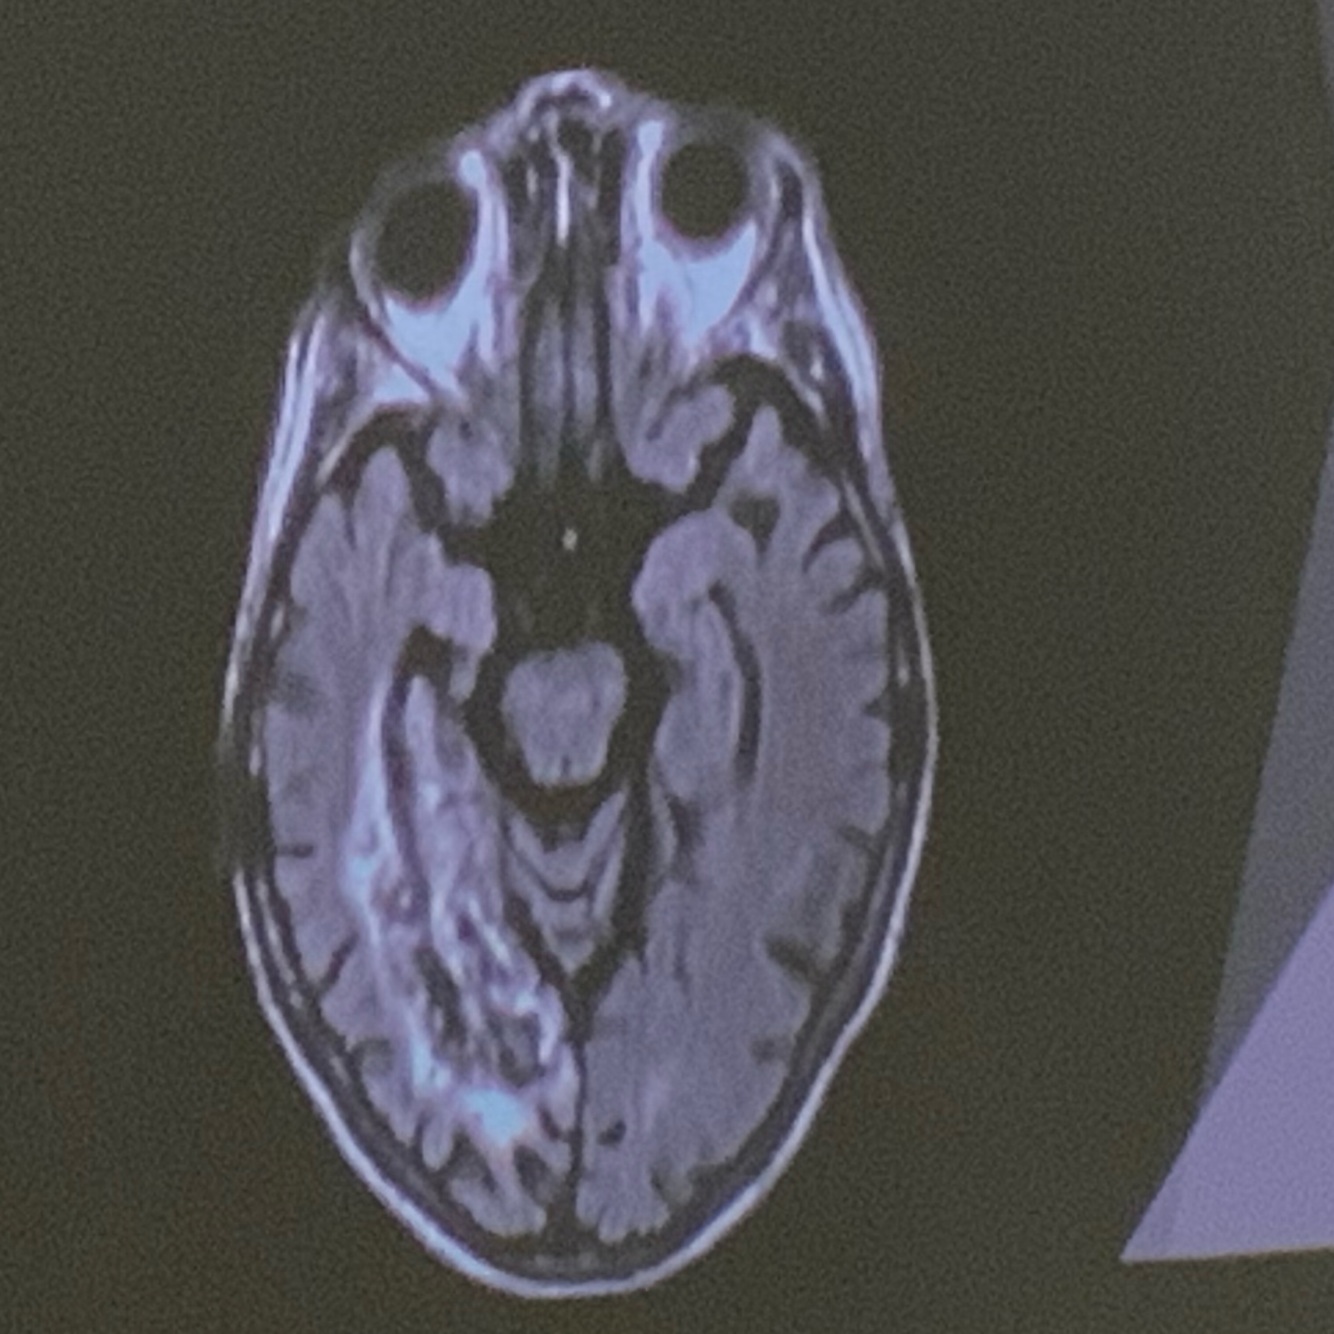

9

Q

Que arteria se encuentra afectada

A

PICA